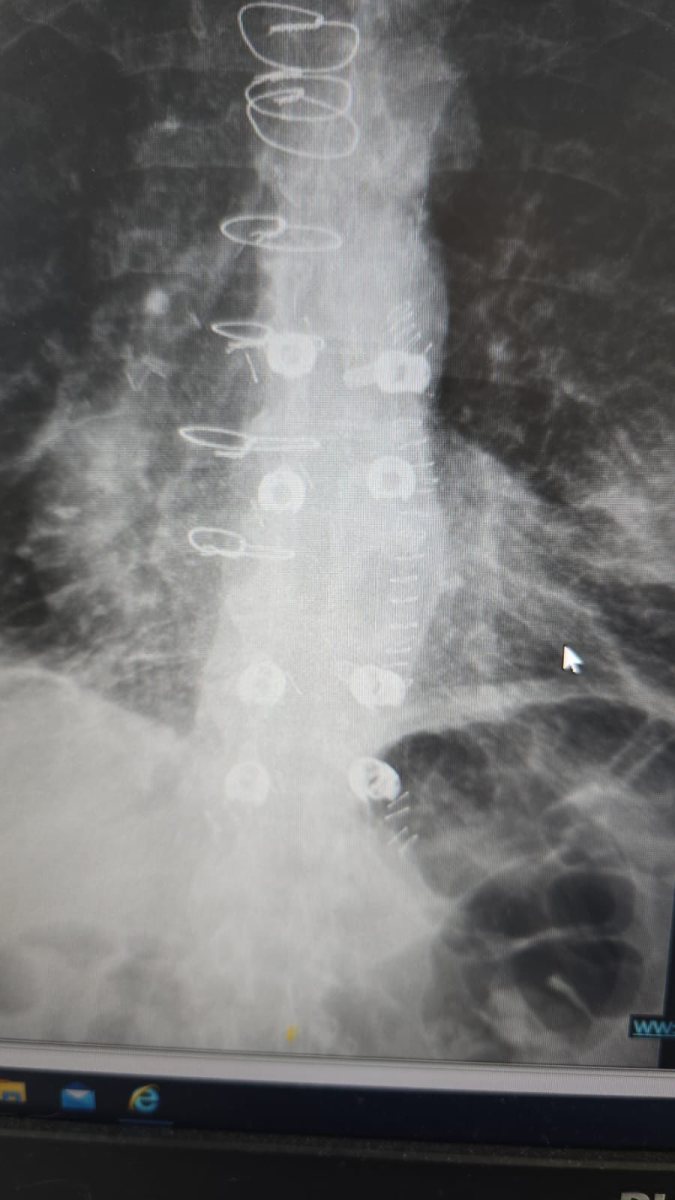

המטופל, גבר בן 60 הלוקה בסרטן ריאה שפיתח גרורה בעמוד השדרה, הגיע למיון בסכנת שיתוק מיידית. במהלך הניתוח הוחדרו 8 ברגים ומוטות מקרבון דרך חתכים של כסנטימטר בלבד, ובמקביל הוסר הגידול שלחץ על חוט השדרה.

הטכניקה להכנסת ברגים בעמוד השדרה דרך חתכים זעירים קיימת כ-30 שנה ומשמשת בעיקר לטיפול בשברים. אולם עד כה לא ניתן היה להשתמש בחומר קרבון בשיטה זו בגלל מאפייניו הפיזיקליים המורכבים. חברת CarboFix הישראלית פיתחה פתרון שמאפשר את השילוב.

שתלי הקרבון אינם יוצרים הפרעות בהדמיות MRI ומפחיתים סיכונים בהקרנות, ומאפשרים לרופאים לכוון את הקרינה בדיוק רב יותר לאזור הגידול.